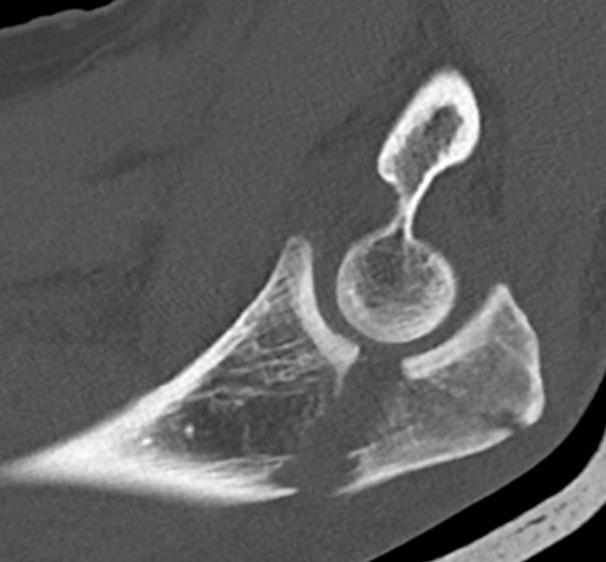

Proximal articular portion of the ulna

- greater sigmoid notch articulates with trochlea

- has a central bare area

Triceps insertion

- attaches to olecranon

- displaces olecranon fragment superiorly